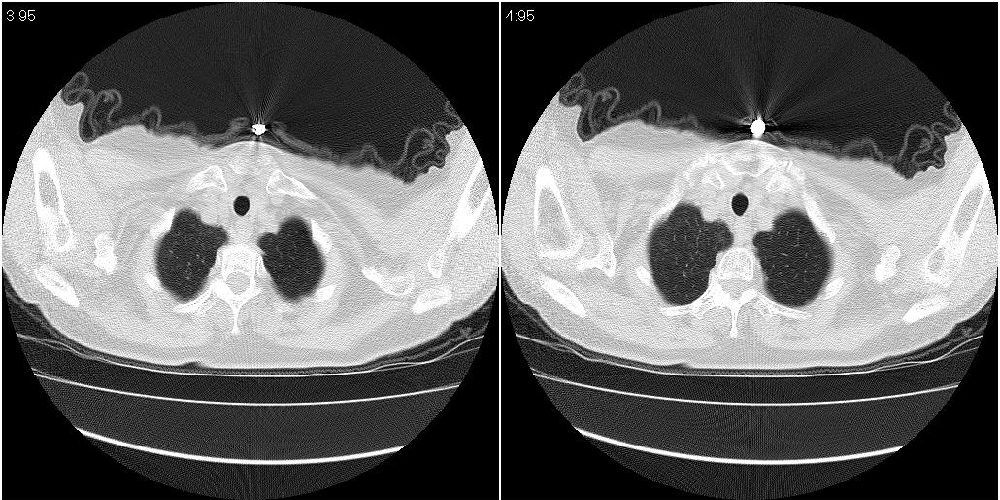

女性,72岁。去年9月份发现肺部病变,诊为肺结核并进行正规治疗至今,但复查后发现ct表现几乎没有变化。

右侧中叶支气管明显狭窄,建议行纤支镜检查!

右中间段支气管局限性狭窄,右中叶支气管亦稍显狭窄,但并未见明显占位表现,半年多了,无变化也许是好事,可能为炎性狭窄,建议继续随访。

双肺继发型tb并右中叶内膜tb,轻度支扩,左下胸膜肥厚粘连。

右中叶炎性改变,支气管狭窄但较光滑,占位可能性不大。

右中间段支气管局限性狭窄,右中叶支气管亦稍显狭窄.

双肺继发性肺结核并右肺中叶节段性肺不张,左下胸膜肥厚粘连。

右肺中叶节段性肺不张,考虑结核或慢性炎症,建议做纤支镜检查。

双肺继发性肺结核并右肺中叶节段性肺不张